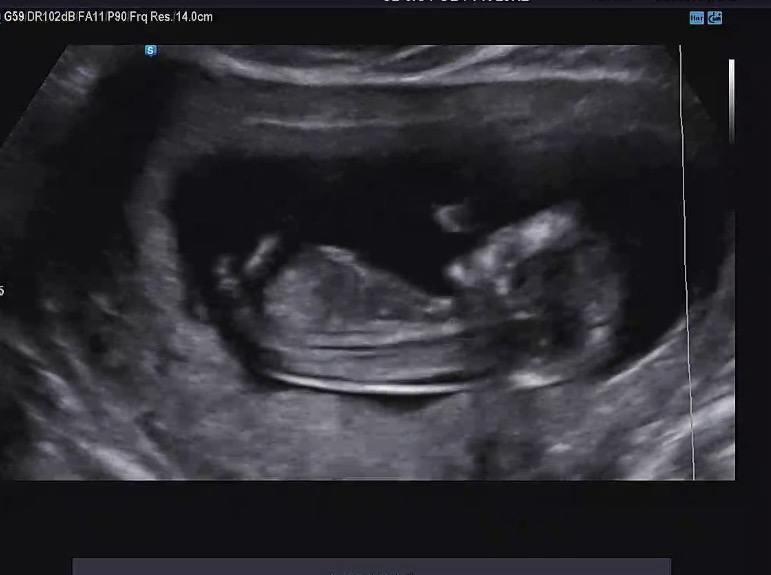

각도법 좀 봐주세용

아들일까요?딸일까요?